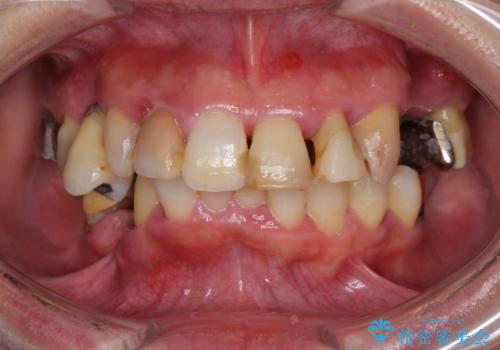

総合歯科治療 → インプラント&根管治療&矯正歯科